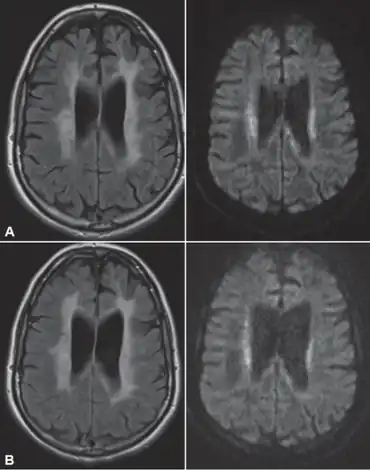

a)Hyperintensities in periventricular and deep white matter b) nine months later, increasing hyperintensities almost entire white matter

Standard MRI scans have been performed on 1.5 Tesla scanners with 5 mm thickness and 5 mm spacing to screen for white matter lesions in identified families. If signal intensities of the MRI scans are higher in white matter regions than in grey matter regions, the patient is considered to be at risk for HDLS, although a number of other disorders can also produce white matter changes and the findings are not diagnostic without genetic testing or pathologic confirmation.[2]